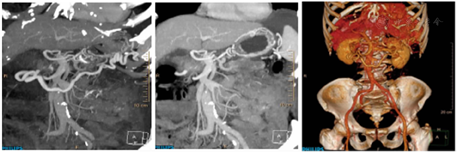

腹部CT三维重建示(图3):(1)胰尾所见,考虑胰腺恶性病变,胰腺癌可能性大。腹膜转移可能。左侧肾上腺转移可能;(2)网膜囊静脉曲张,考虑胰源性区域性门静脉高压所致,脾静脉局部显示欠佳。